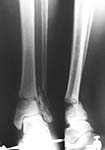

Thank you all for the kind responses. Kindly find attached the post op picture. I did an Ilizarov ring fixation which extended to the calcaneum. There was multiple small areas of partial thickness skin necrosis anteriorly and laterally which required split thickness skin graft.

Ilizarov device is a good choice, but I'm concerned about the valgus angulation (> 15degrees ?).

i would therefore, as a general rule, try my utmost to put in more wires in the distal fragment to gain a good hold + compression across the fracture site adds a lot to the stability of the frame. usually, in stable configuration of fractures, like your patient has, the calcaneal fixation then becomes redundant. you would need to compress this fracture further, judging from the xrays